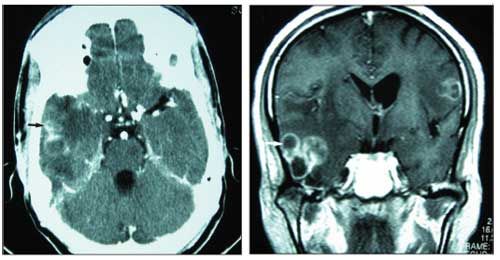

The patient's health did not improve with this therapy, and his neurocognitive function continued to deteriorate. New brain imaging studies were obtained 12 days after the initiation of his anti-Toxoplasma treatment: This brain CT scan showed multiple ring-enhancing lesions within the right temporal lobe and cerebellum. The MRI scans of the brain also showed multifocal ring-enhancing lesions within the brain and right mastoid region, with evidence of conglomeration within the right temporal region (Figure 3). These findings suggested bacterial abscesses. Both imaging studies showed that the lesions had progressed since the examination performed 12 days earlier despite treatment for toxoplasmosis.

Figure 3.MRI scans of the brain showing multifocal ring enhancing lesions within the brain and right mastoid region.